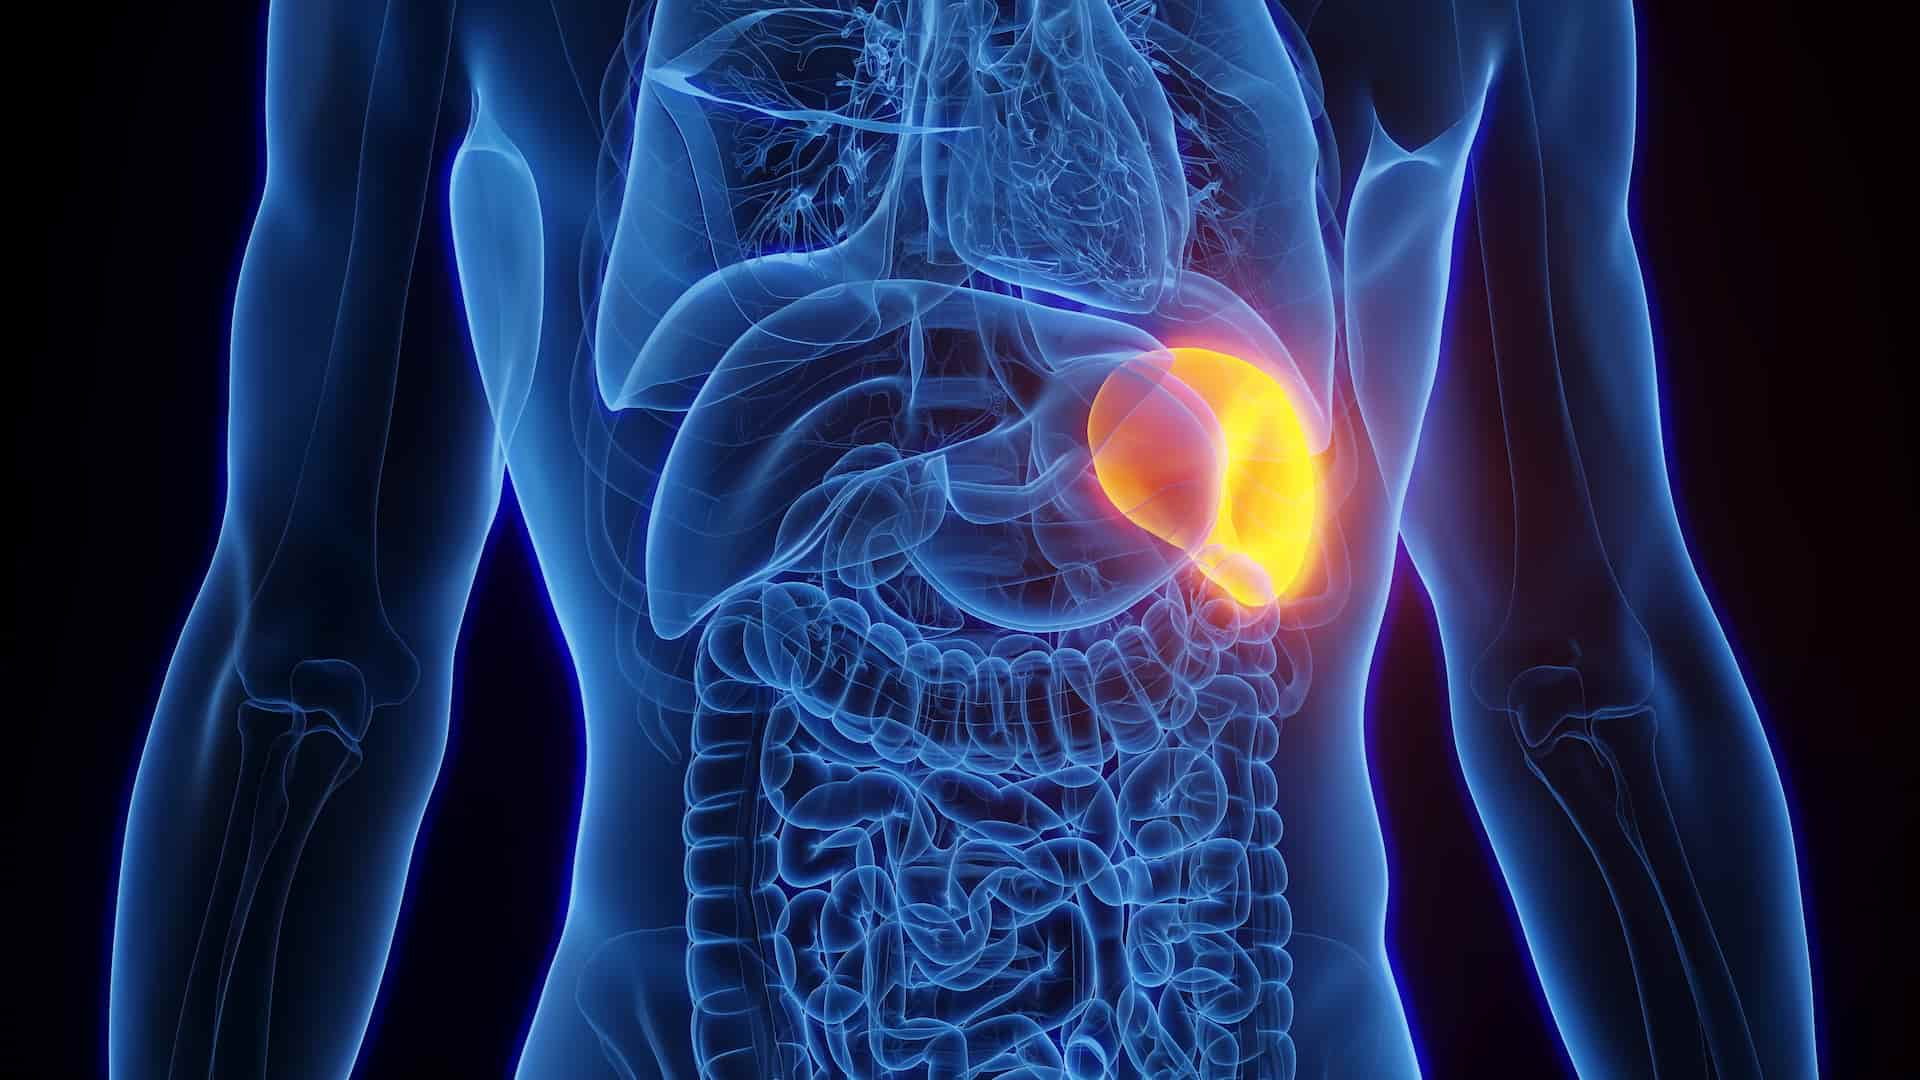

Селезінка ховається тихо під лівим ребром, фільтруючи кров і борючись з загарбниками, але коли вона роздувається, як переповнений резервуар, це сигнал тривоги. Найчастіше збільшена селезінка, або спленомегалія, виникає через інфекції, проблеми з печінкою чи захворювання крові, змушуючи орган працювати на межі. У дорослих це може бути портальна гіпертензія від цирозу, у дітей – вірусний мононуклеоз, а загалом до 2% населення стикається з таким станом, за даними медичних оглядів.

Розмір селезінки в нормі не перевищує 12 см у довжину, але при спленомегалії вона виростає, тиснучи на сусідні органи й викликаючи дискомфорт. Цей процес не буває випадковим – селезінка реагує на перевантаження антигенами, застій крові чи інфільтрацію шкідливими клітинами. Розберемося, що саме провокує цей “бунт” органу, крок за кроком.

Селезінка – це не просто “додаток” до імунної системи, а справжній фільтр, який щодня пропускає через себе весь об’єм крові, нищачи старі еритроцити, бактерії та продукуючи антитіла. Коли її вага перевищує 200 грамів чи довжина сягає понад 13 см на УЗД, лікарі діагностують спленомегалію. Легкий ступінь часто безсимптомний, помірний – пальпується під ребрами, масивний (понад 20 см) видно на око й загрожує розривом.

Ви не відчуєте її щодня, бо нормальна селезінка м’яка й еластична, прилягає до шлунка та нирки. Але при набряку капсула розтягується, з’являється тупий біль, що іррадіює в плече. Механізм простий: орган гіпертрофується, реагуючи на стрес, і це може бути як тимчасовим явищем, так і хронічним сигналом серйозної патології.